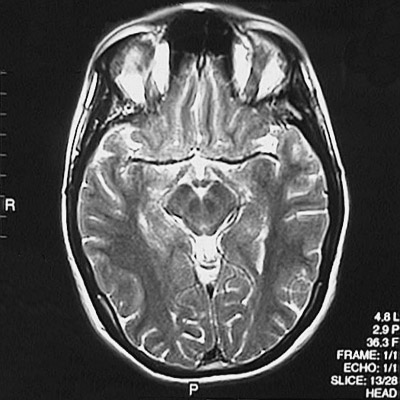

This is a normal axial T2 weighted MRI scan demonstrating the inferior frontal lobe and temporal lobe and occipital lobe and cerebral peduncle and substantia nigra and red nucleus and aqueduct of Sylvius and frontal sinus and orbit.